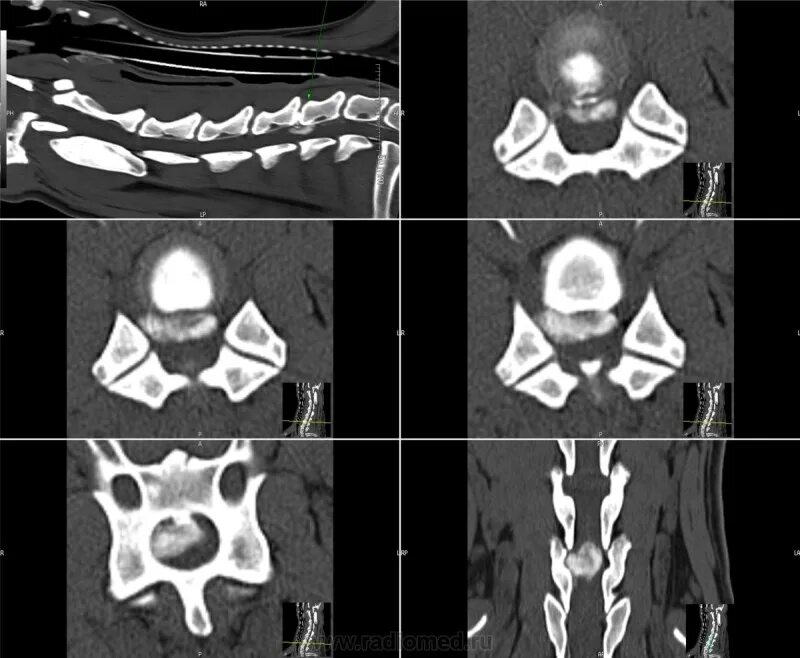

Грыжи на кт